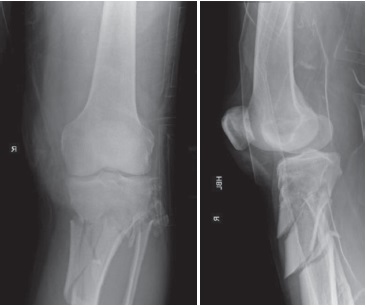

A 72-year-old male was severely injured in a road traffic accident, whereby his leg was trapped between a moving car and stationary vehicle. Plain X-rays and CT angiogram identified a comminuted proximal tibial fracture with transection of the popliteal artery and vein (Figure 1). He presented with severe hypotension, delayed capillary refill, and an absence of pedal pulses. Initial emergency treatment included fasciotomies, external fixation, and vascular primary repair conducted on the day of admission. Initially an external fixator was applied to give stability (Figure 2, 3). The patient was then turned prone and the popliteal artery was repaired primarily following a posterior approach. The patient’s post-operative period in the Intensive Care Unit (ICU) was complicated by an acute kidney injury due to rhabdomyolysis, his creatinine kinase at the time was 34.617 U/L (reference range 39-308). His rhabdomyolysis was managed by the ICU team with fluid resuscitation and diuretics, he did not require dialysis.

Figure 2. Three-dimensional reconstruction of images from CT angiogram demonstrating interrupted flow of the right popliteal artery